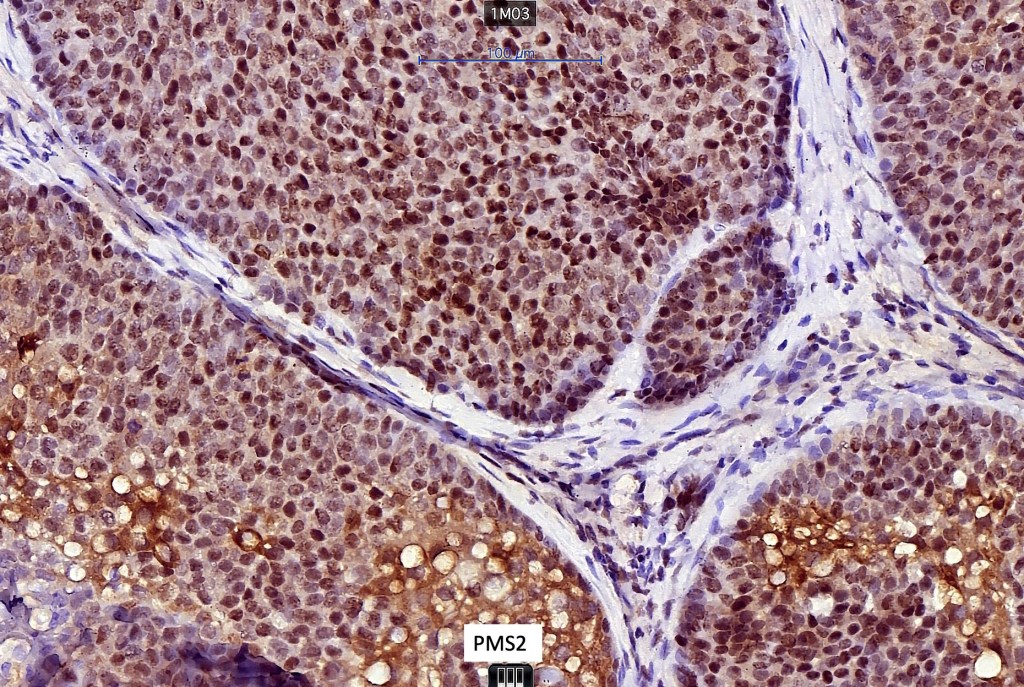

•Sebaceous carcinoma may be a manifestation of Muir-Torre syndrome particularly those arising in outside the head and neck

Immunohistochemistry (from the Muir-Torre patient except for EMA which was shared by Dr. Tsheri Dorji